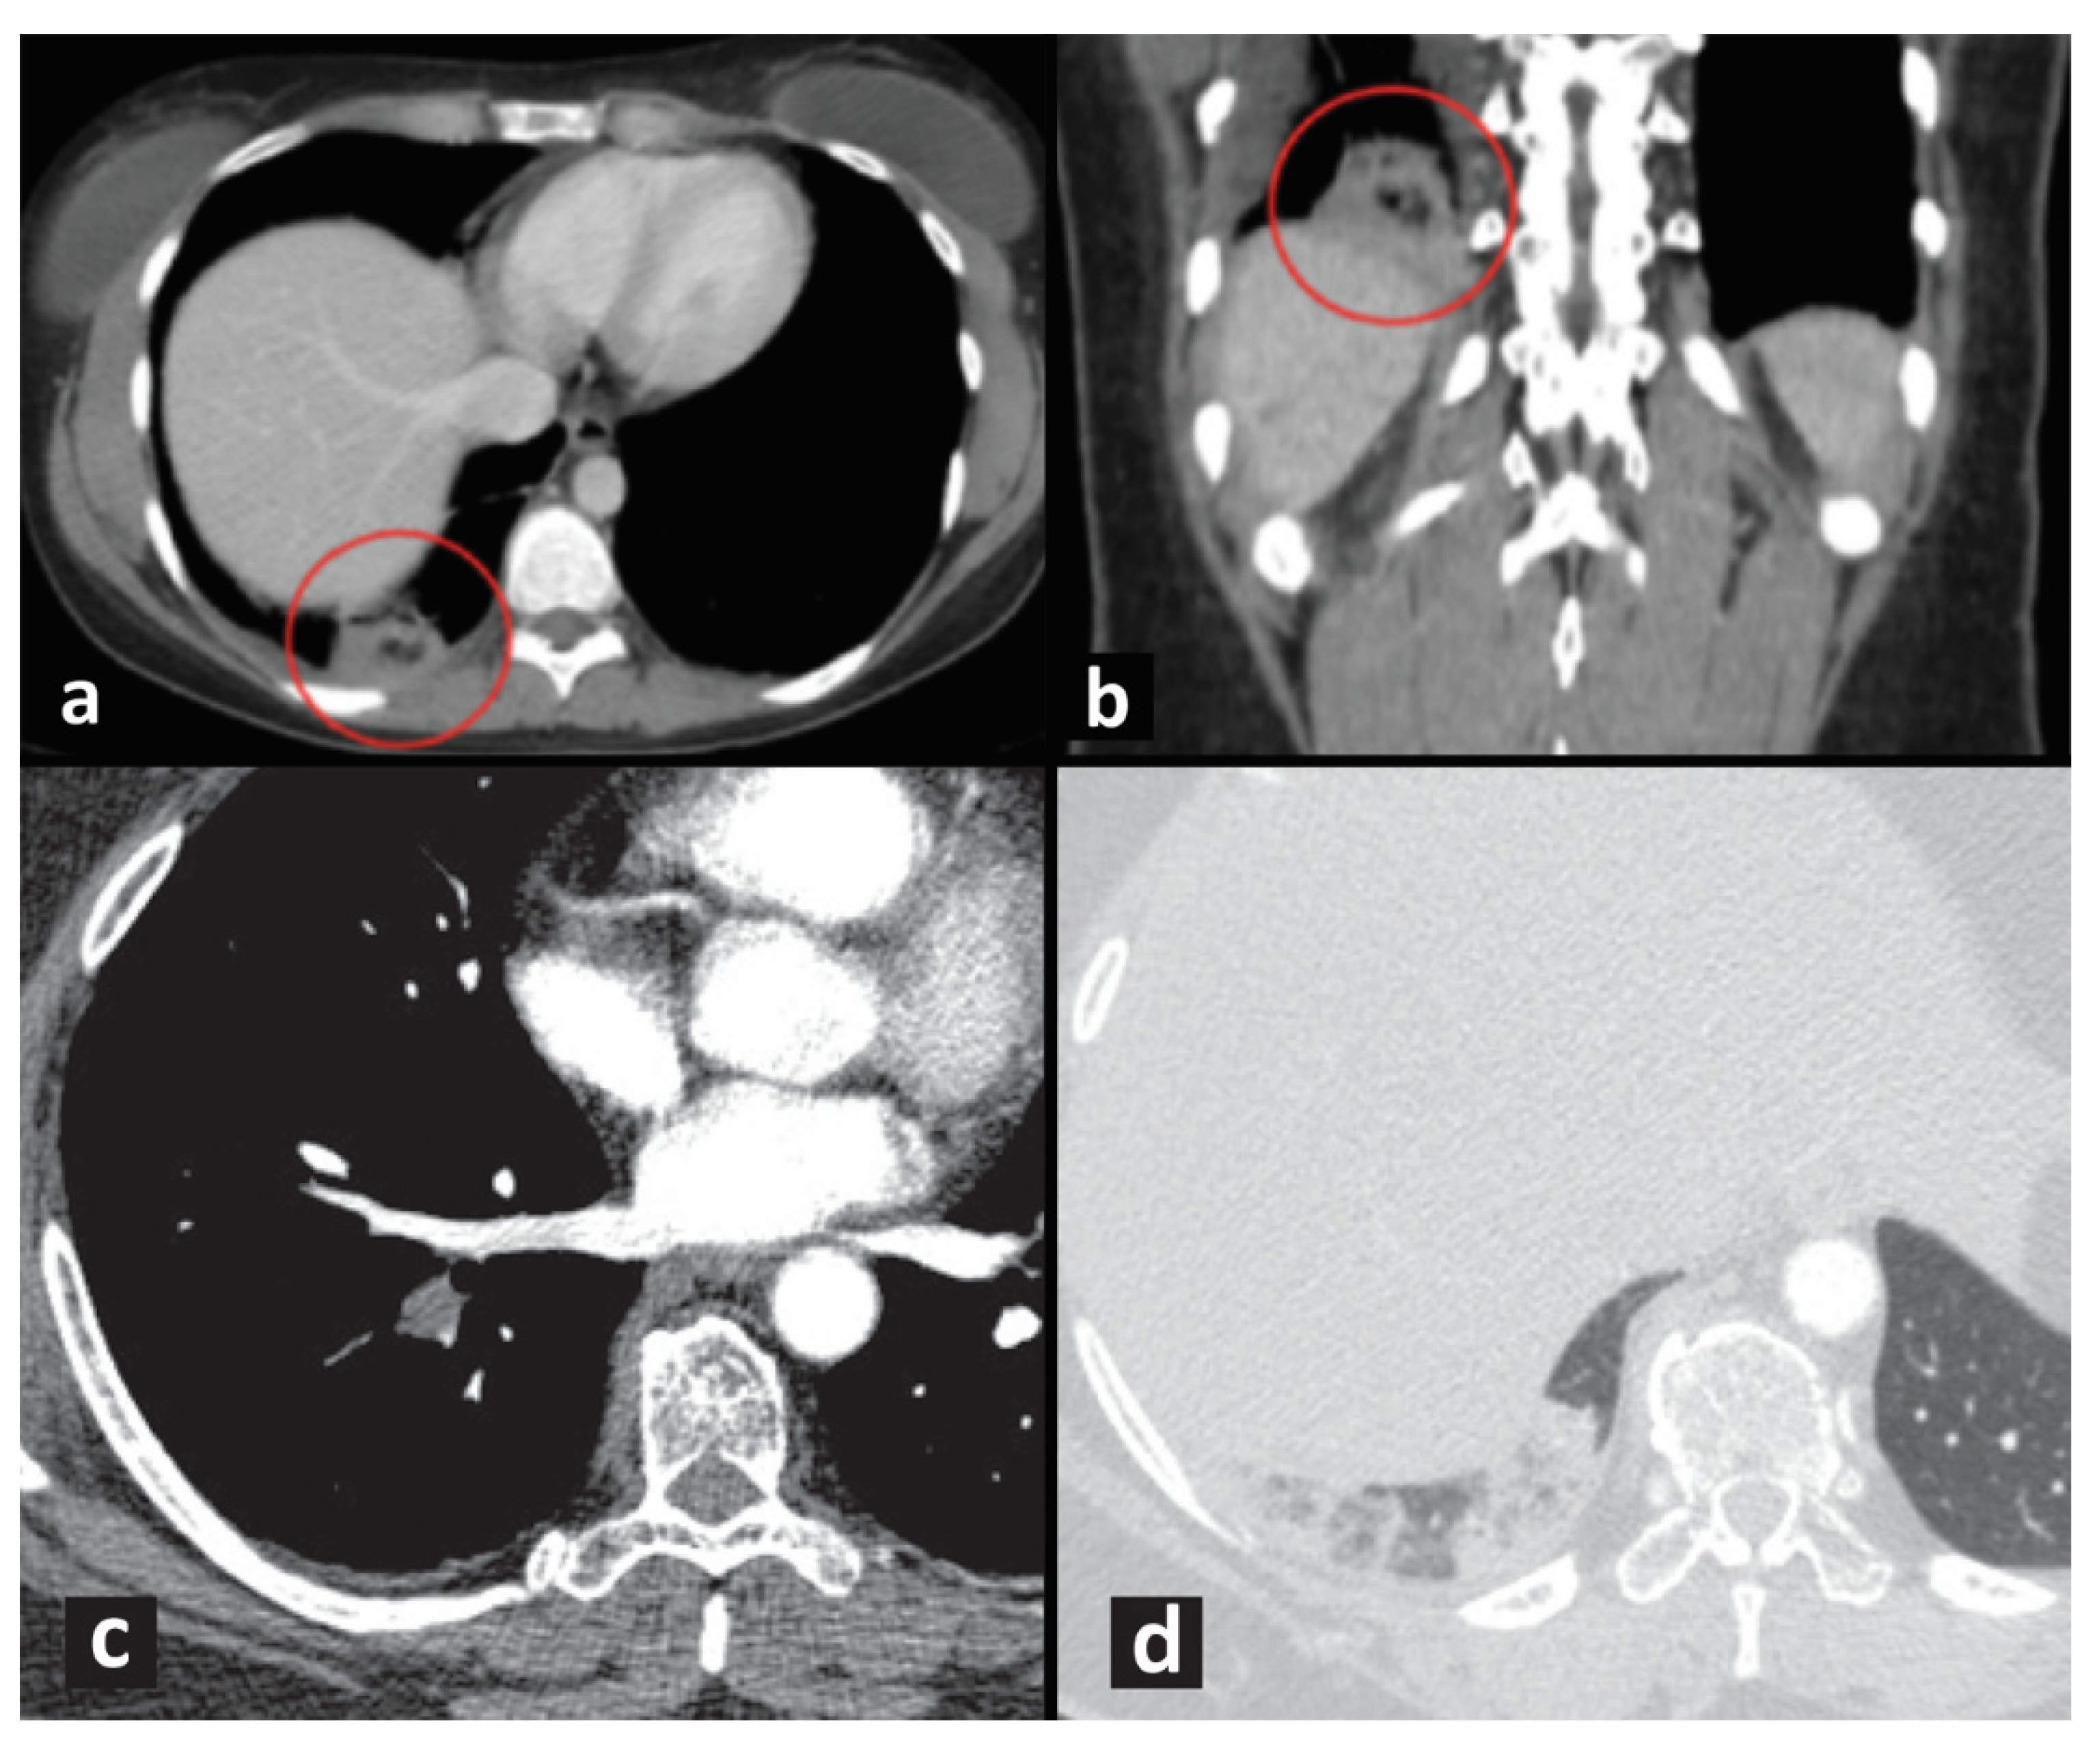

- Revel, M.P.; Triki, R.; Chatellier, G.; Couchon, S.; Haddad, N.; Hernigou, A.; Danel, C.; Frija, G. Is It possible to recognize pulmonary infarction on multisection CT images? Radiology 2007, 244, 875–882. [Google Scholar] [CrossRef] [PubMed]

- Dandamudi, S.; Palaparti, R.; Chowdary, P.; Kondru, P.; Palaparthi, S.; Koduru, G.; Ghanta, S.; Mannuva, B. “Bubbly lung consolidation”—A highly specific imaging marker for pulmonary infarction. J. Dr. NTR Univ. Health Sci. 2020, 9, 273–275. [Google Scholar] [CrossRef]

- Fosmire, S.T.; Gibson, G.N.; Copeland, J.C.; Maydew, M.S.; Eggers, C. Pulmonary Infarction: Right Upper Quadrant Pain as a Presenting Symptom with Review of Typical Computed Tomography Imaging Features. Mil. Med. 2018, 183, e779–e782. [Google Scholar] [CrossRef] [Green Version]